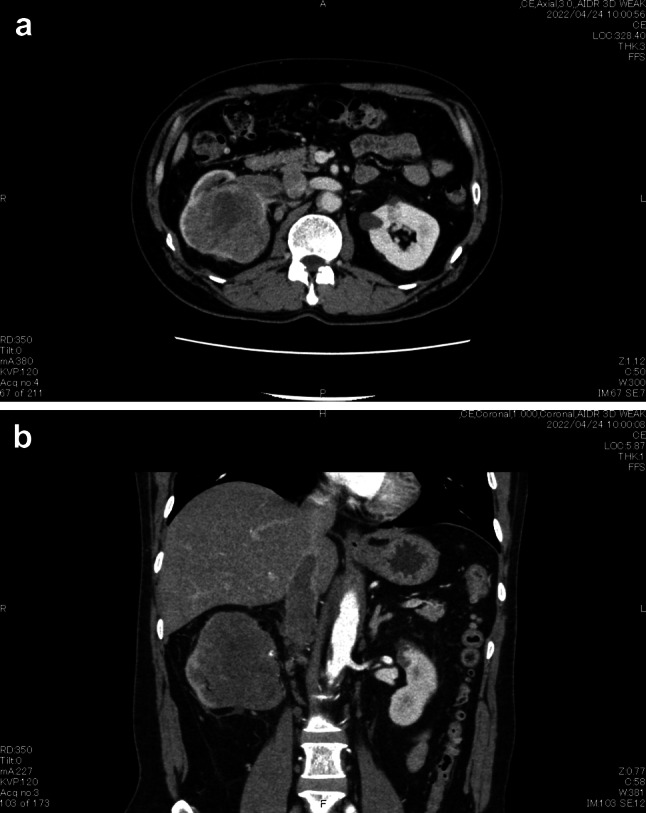

我们在此介绍一位并发下腔静脉瘤栓的肉瘤型肾细胞癌患者,我们用尼伐单抗加伊匹单抗进行了治疗。治疗的结果是肿瘤缩小,从而能够通过机器人辅助腹腔镜根治性肾切除术完全切除肿瘤。患者目前仍健在,没有复发迹象。

We here present a patient with a sarcomatoid renal cell carcinoma complicated by inferior vena cava tumor thrombus that we treated with nivolumab plus ipilimumab. This resulted in shrinkage of the tumor, enabling complete resection by robot-assisted laparoscopic radical nephrectomy. The patient is still alive with no evidence of recurrence.